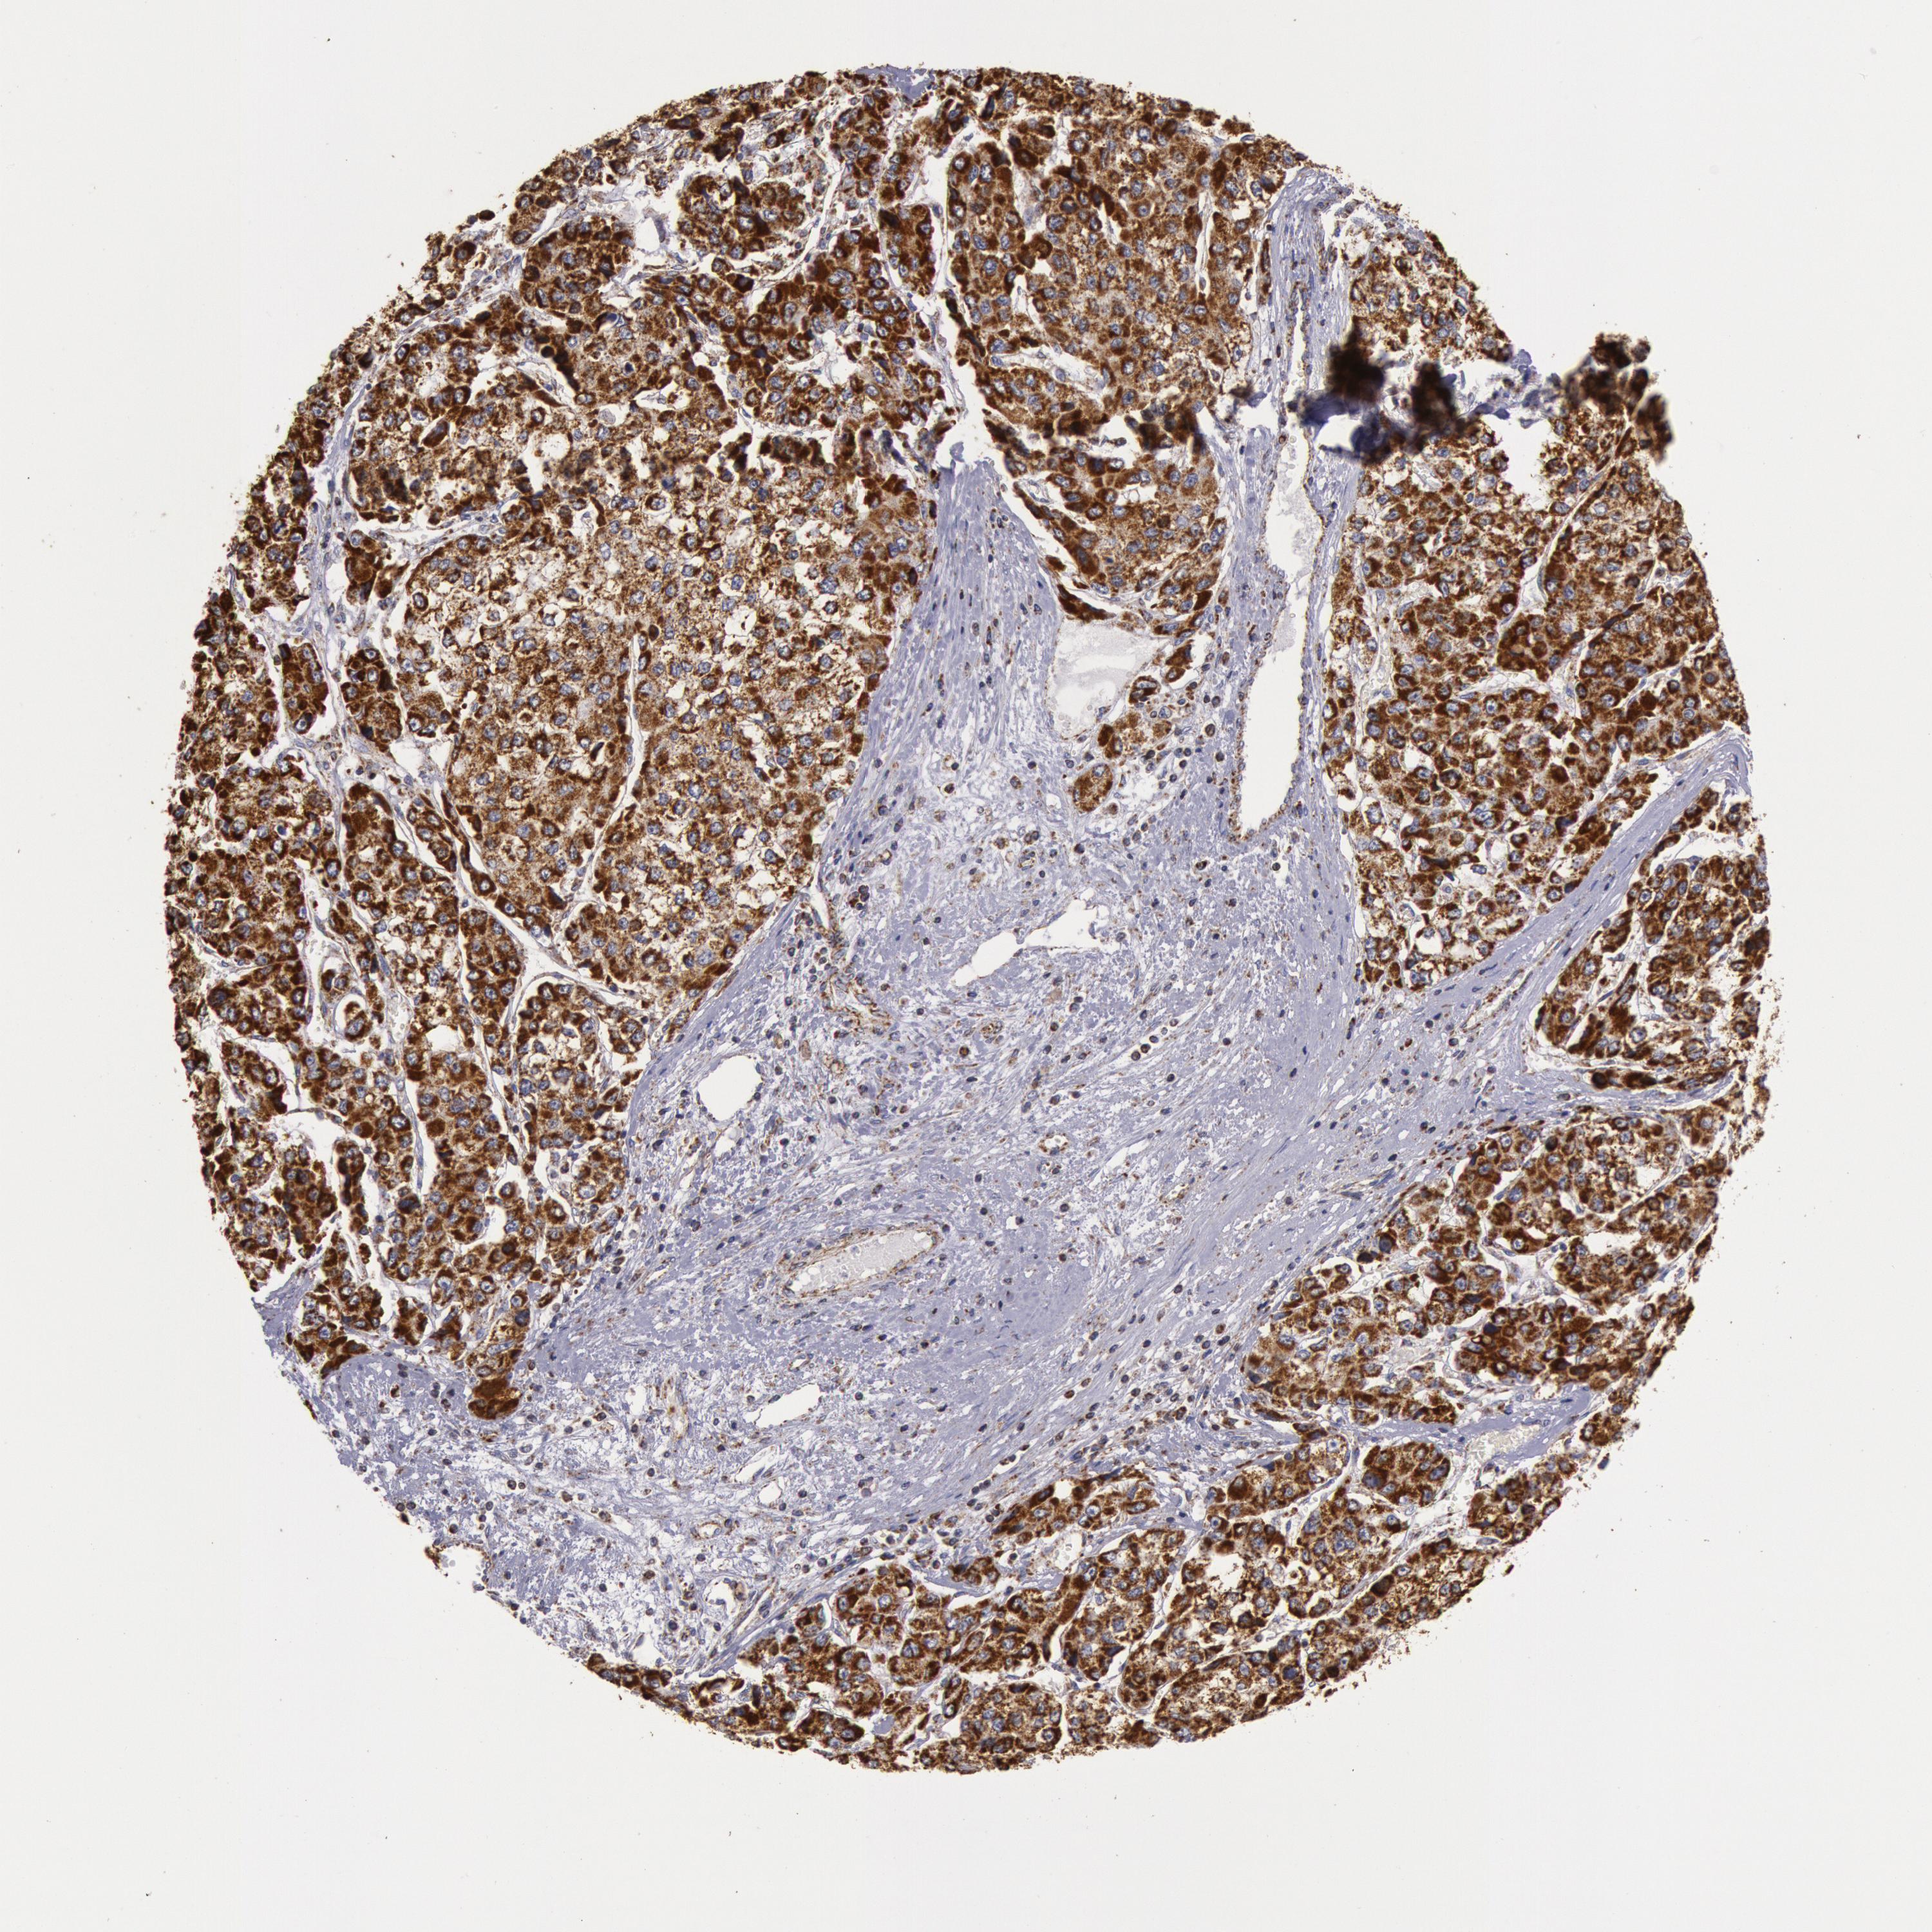

LIVER CANCER - Protein expressioni

A mouse-over function shows sample information and annotation data. Click on an image to view it in a full screen mode. Samples can be filtered based on level of antibody staining by selecting one or several of the following categories: high, medium, low and not detected. The assay and annotation is described here.

Note that samples used for immunohistochemistry by the Human Protein Atlas do not correspond to samples in the TCGA dataset.

Antibody stainingi

Antibody staining in the annotated cell types in the current human tissue is reported as not detected, low, medium, or high, based on conventional immunohistochemistry profiling in selected tissues. This score is based on the combination of the staining intensity and fraction of stained cells.

Each image is clickable and will lead to virtual microscopy that enables deeper exploration of all samples and also displays staining intensity scores, fraction scores and subcellular localization as well as patient and tissue information for each sample.

Antibody HPA001247

Staining

High

Medium

Low

Not detected

Intensity

Strong

Moderate

Weak

Negative

Quantity

>75%

75%-25%

<25%

None

Location

Nuclear

Cytoplasmic/membranous

Cytoplasmic/membranous,nuclear

Carcinoma, Hepatocellular, NOS

Cholangiocarcinoma